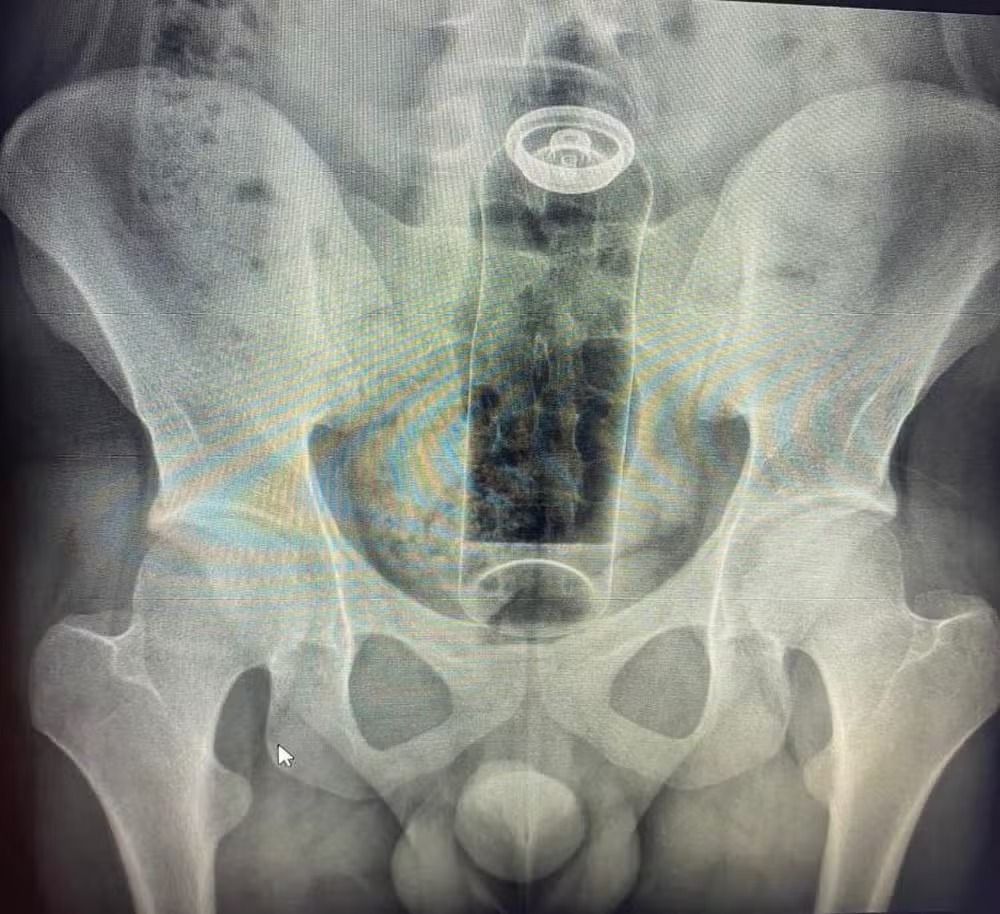

Um jovem de 19 anos foi internado após ficar com um desodorante preso no reto durante uma “brincadeira” sexual, segundo relato do cirurgião coloproctologista Daniel Brosco. O médico usou as redes sociais para alertar sobre os riscos do uso de objetos não apropriados para a região anal.

De acordo com Brosco, o paciente informou que tentou retirar a embalagem em casa, mas não conseguiu. O especialista afirma que o uso de objetos inadequados pode causar perfurações, infecções graves e, em casos extremos, levar à morte. “A fantasia não é um problema. O problema é não usar objetos específicos para isso”, disse o médico em reportagem do G1.

O coloproctologista relata que casos semelhantes têm se tornado mais frequentes e cita atendimentos recentes envolvendo batata, partes de cadeira, garrafa de vidro e plug anal. Ele explica que objetos podem ser “sugados” para dentro do intestino pelos movimentos peristálticos ou pelo vácuo formado no reto.